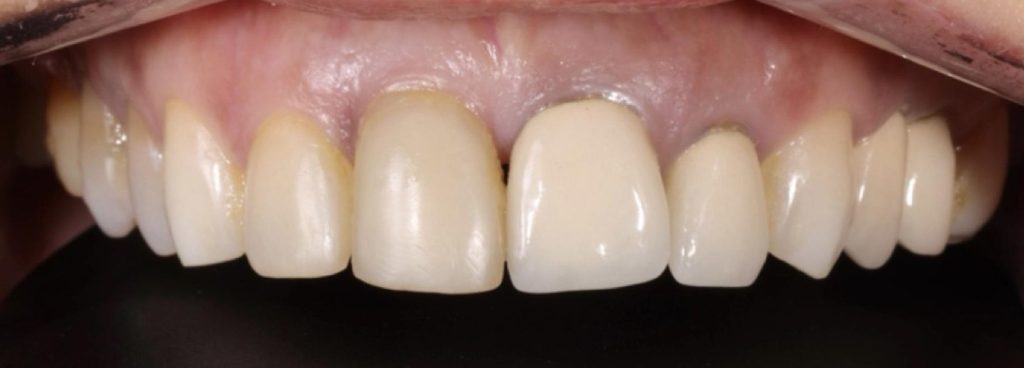

Pod kierownictwem lek. stom. Michała Badowskiego po wnikliwej analizie została przeprowadzona korekta dziąseł i pozbycie się nieestetycznych koron na podbudowie metalowej, eliminując tym samym nawracające stany zapalne dziąseł.

Następnie została wykonana wizualizacja nowego uśmiechu, idealnie dopasowana do twarzy Pacjentki. Po jej akceptacji, przygotowaliśmy komplet koron i licówek pełnoceramicznych na górne i dolne zęby.

Całe leczenie trwało zaledwie 3 miesiące!

Dzięki współpracy lek. stom. Michała Badowskiego i techn. dent. Joanny Gancarz z laboratorium Dentalscan Pacjentka zachwyca pięknym uśmiechem!